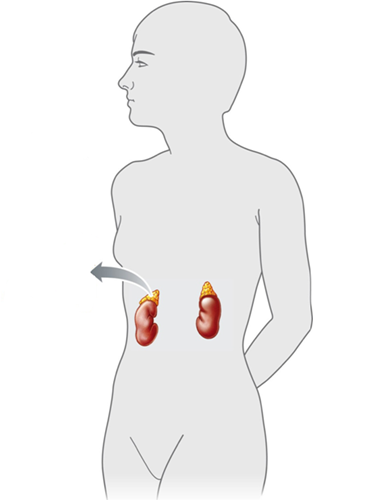

-Answer the question using the accompanying figure. The ____ glands are shown in this figure.